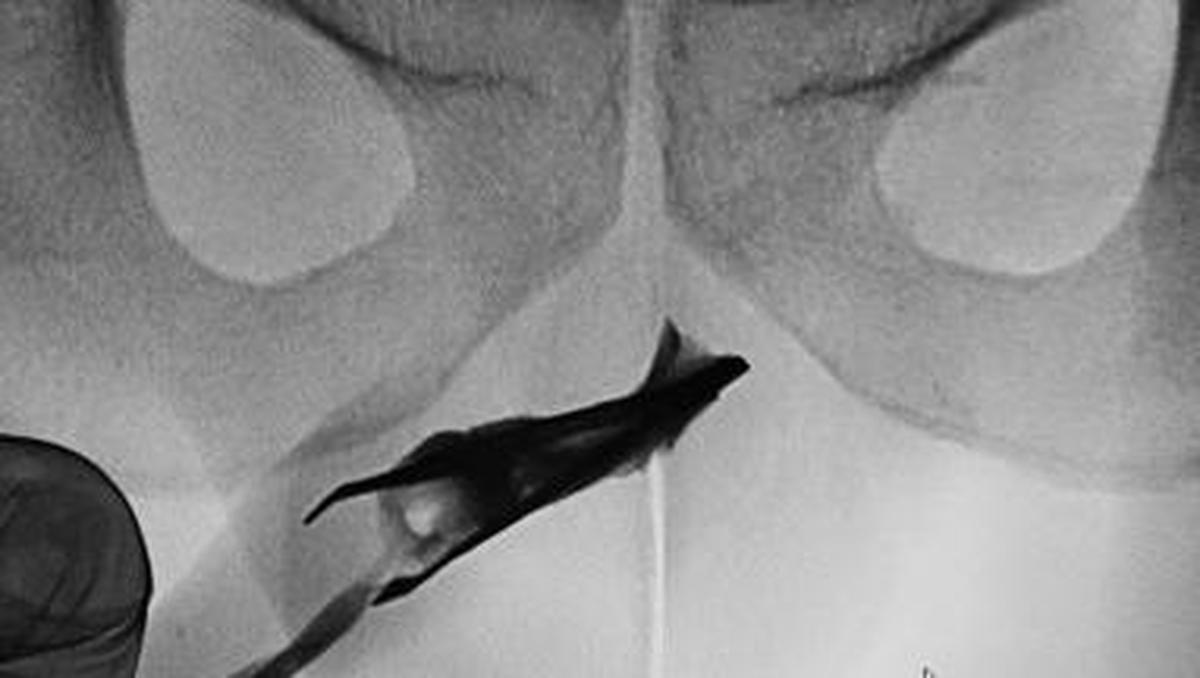

Jakarta – Seorang pasien pria berusia 22 tahun Hingga Arab Saudi datang Hingga Ahli Kemakmuran Didalam pinset yang menyangkut Hingga penisnya. Benda itu ternyata sudah ada Di 4 tahun.